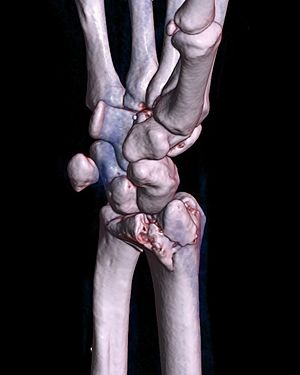

A palmar Barton's fracture of the right wrist, as shown on a 3D-rendered CT scan

A Barton fracture is a type of wrist injury where there is a break of the front or back of the radius nearest the hand, resulting in the wrist being pushed out of place.[1] It typically occurs after falling on on top of a bent wrist.[2]

There exist two types of Barton's fracture – dorsal[3] and palmar, the latter being more common. The Barton's fracture is caused by a fall on an extended and pronated wrist increasing carpal compression force on the dorsal rim. Intra-articular component distinguishes this fracture from a Smith's or a Colles' fracture.